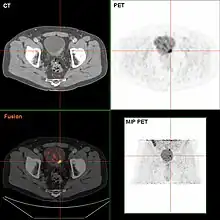

Bladder tumor in FDG PET due to the high physiological FDG-concentration in the bladder, furosemide was supplied together with 200 MBq FDG. The uptake cranial to the lesion is a physiological uptake in the colon.

If invasive or high grade (includes carcinoma in situ) cancer is detected on TURBT, an MRI and/or CT scan of the abdomen and pelvis or urogram and CT chest or x-ray chest should be conducted for disease staging and to look for cancer spread (metastasis). Increase in alkaline phosphatase levels without evidence of liver disease should be evaluated for bone metastasis by a bone scan.[1] Although 18F-fluorodeoxyglucose (FDG)-positron emission tomography (PET)/CT has been explored as a viable method for staging, there is no consensus to support its role in routine clinical evaluations.[54]